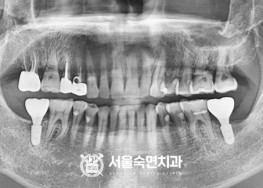

임플란트-치료-전후사진